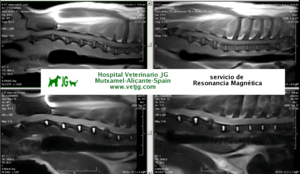

Detalle de los primeros segmentos de la columna vertebral torácica en un perro. Resonancia magnética |